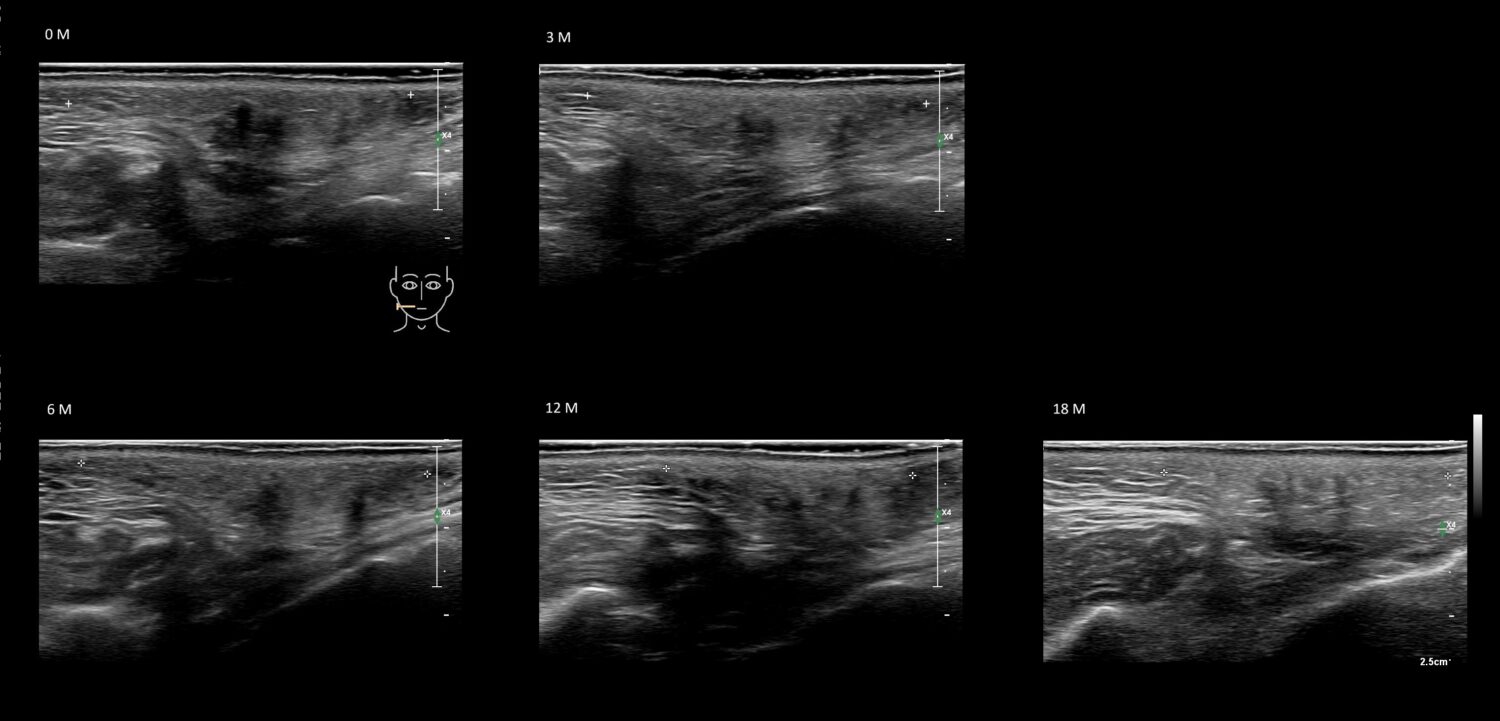

Fillers

Draw in the second image below where the fillers are located. To check if your answer is correct, swipe the first image to the right.